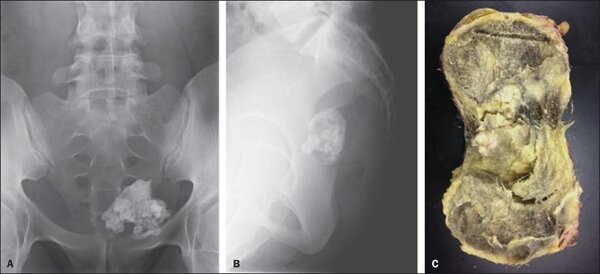

Недавно в новостях появилась информация о необычном медицинском случае: у 13-летнего подростка из яичка был удален зуб. Это не шутка, а реальный факт, подтвержденный врачами. Школьник сам обнаружил у себя уплотнение и обратился за помощью. После обследования в Морозовской детской больнице Москвы врачи провели срочную операцию, ожидая увидеть опухоль. Однако вместо новообразования они извлекли полностью сформированный жевательный зуб — седьмой нижний моляр, соответствующий возрасту 10–12 лет.

Это явление объясняется тератомой — опухолью, которая может содержать различные ткани и даже органы. Тератомы яичек и яичников встречаются не так редко, примерно у одного из 35 000 новорожденных. Но природа иногда преподносит поистине удивительные «сюрпризы».

Отдельного внимания заслуживают случаи обнаружения зубов в яичниках или матке у женщин. Как ни странно, это встречается довольно часто. Палеонтологи нашли доказательства, что подобные аномалии существовали и в древности: зубы в яичнике были обнаружены у женщины, похороненной в Древнем Риме, а также в захоронении XV века в Португалии. В последнем случае опухоль содержала четыре моляра и один клык.